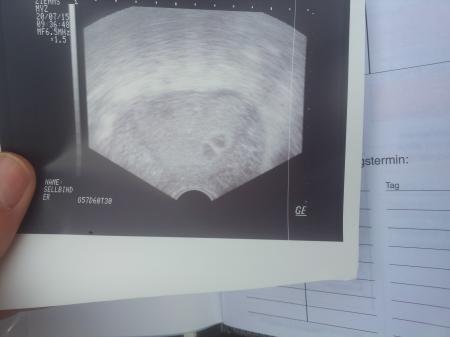

5+4 ssw arzt sagt es koennten mal zwei gewesen sein aber das oben drueber hatte auch etwas drin also sind eher die Zwin. Mutti`s gefragt wenn es nur eins ist das auch nicht schlimm habe schon 6 kinder aber mummig ist einen schon wenn es zwei sind .Muss am 21.7 wieder Ultraschall bin gespann .

Bild zu Bitte mal schauen eins oder zwei ? - Schwanger - wer noch? Rund um die Schwangerschaft

Also bei mir sah es so in der ersten schwangerschaft aus und bei mir war das runde die fruchthöhle und das andere ein Hämatom. Drück dir die Daumen.

Ich bin mit Zwillis schwanger... Kann gut sein. Ist noch viel zu früh! Bei mir hat man das zweite Fruchthöhle erst später gesehen, da war nur etwas "angdeutet" in der FH. 11 Tage später schlagen beide Herzchen :) ABER es ist wirklich noch viel zu früh! Leider heißt es abwarten und Tee trinken :( Alles gute

Also ich war definitiv mit 2en schwanger und war auch in der 5 ssw. Man konnte schön und deutlich 2 Fruchthöhlen und Dottersack sehen Aber deines sieht eher aus wie flüssigkeit?! Da hilft wohl nur abwarten, ich weiß... Auch nicht meine Stärke Nun hat sich nur eines entwickelt

Für mich sieht eines leer aus. Allerdings habe ich noch nie Zwillinge in der frühen Woche gesehen, ich hatte bis heute (zum Glück ) immer nur einlinge. Wünsche dir, dass das kommt, was du dir wünscht und alles gesund ist, egal ob 1 oder 2 Babys.

Es könnte auch ein Hämatom sein... jedenfalls sah meins damals so ähnlich aus.. aber wer weiß :) vielleicht zeigt sich beim nächsten mal direkt ein 2. Herzschlag !! Alles Gute euch !

Würde auch sagen eine fruchthöhle und ein Hämatom